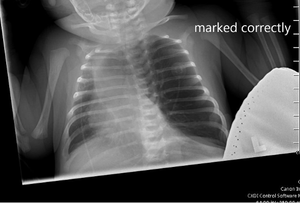

On physical examination, the patient appeared to be in significant respiratory distress. Her oxygen saturation was 96% on high-flow nasal cannula.

Can you diagnose this patient? Take our poll and find out! Then check back for the full case, differential diagnosis, and correct diagnosis.